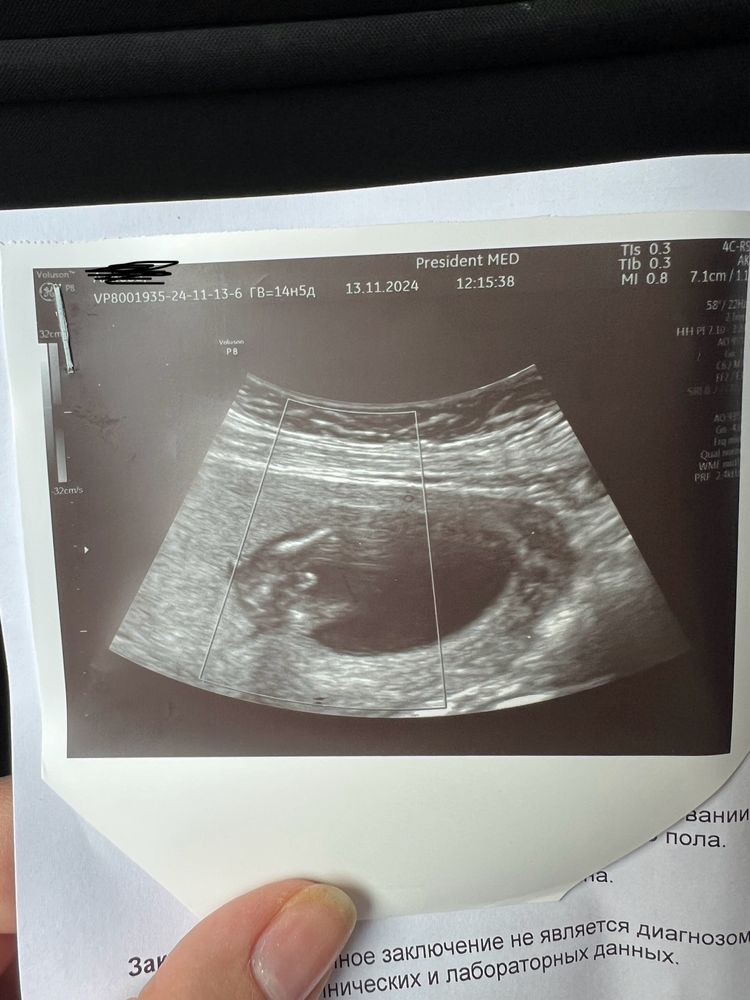

Изображение Девочки, кого видите, мальчик или девочка?

Екатерина, у вас какая неделя?

Нида, по узи 18 недель , акушерский 17 недель 🤷‍♀️ 😄

Екатерина, А вам не сказали пол на такой неделе?

Нида, это был первый скрининг , жду второй На первом не сказали

Екатерина, но я думаю Что девочка, обычно у мальчика прям видно на такой неделе